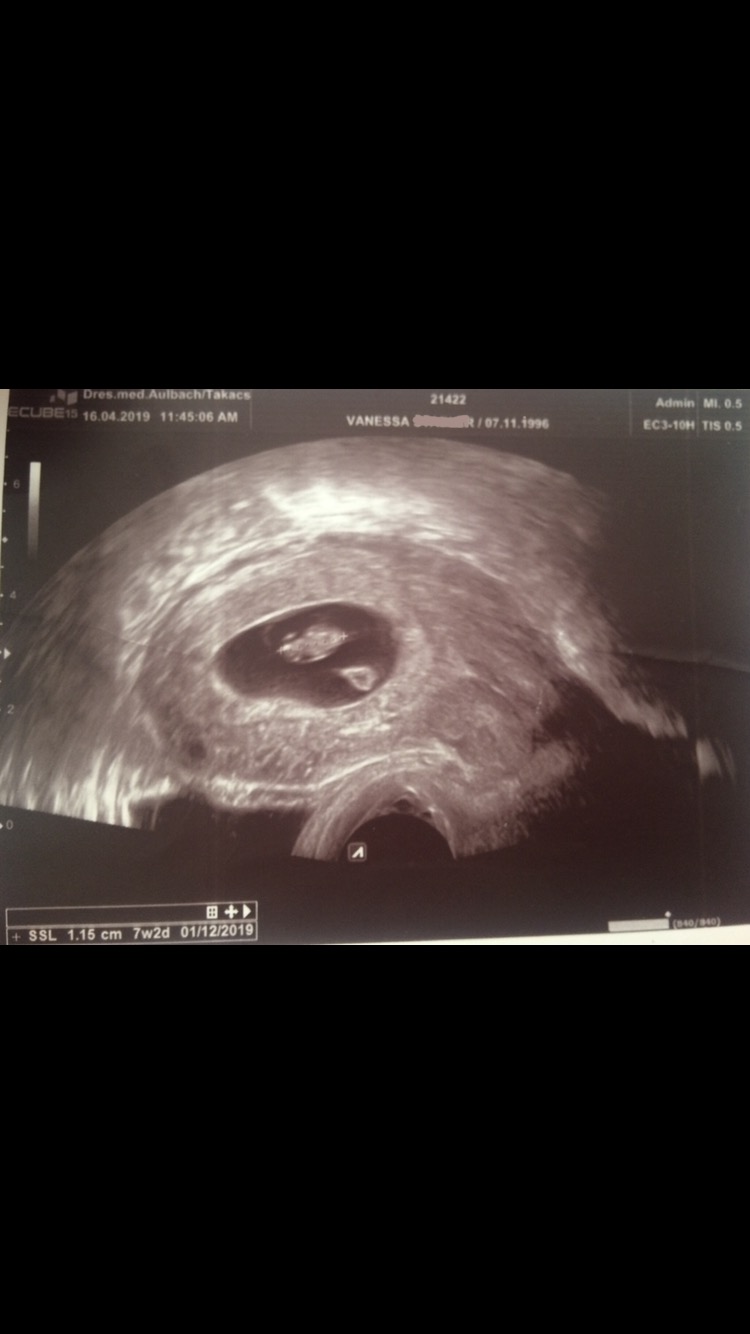

• Heute ist einer der schönsten und überwältigender Tage die ich in meinem jungen Leben je erleben durfte ...

Es ist der 16.04.2021. heute genau vor 2 Jahren also am 16.04.2019 haben wir von Philipp erfahren. Ich war schwanger 🥰

Ich musste ab 01.05 ins beschäftigungsverbot und konnte die Schwangerschaft zuhause genießen. Es war auch genau 10 Tage vor dem Geburtstag meines Mannes.

Und jetzt .. heute 2 Jahre später steh ich leer da. Er wurde uns nach nur 16 Monaten genommen. Warum 😭😭😭